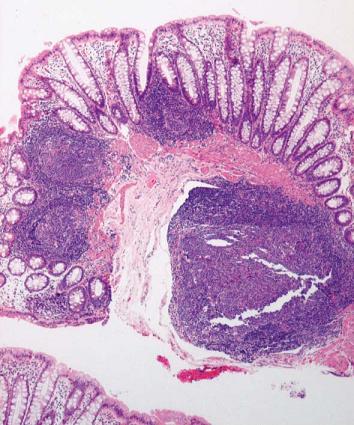

It is also vitally important to determine when a biopsy is insufficient or inadequate for diagnosis. Anatomically, the lower level of sampling is should be one or ideally 2 cms above the pectinate line. Biopsies which are very low or close to the anal sphincter may not have ganglion cells even when the patient does not have aganglionosis. When ganglion cells are not observed in a biopsy and there are islands of squamous epithelium or sphincter muscle fibers, it is the unequivocal signature that the sample was obtained from below the pectinate line. This should always be reported as a sample which is inadequate for diagnosis. If in doubt about the sampling site, I recommend making a note to remind the clinician and avoid misinterpretations. From the histological point of view a rectal biopsy is considered appropriate when the amounts of mucosa and muscularis mucosa together are equivalent in thickness to the amount of submucosa (Figure 6) (10). If the amount of submucosa in the sample is good, but it contains a lymphoid follicle, this must also be considered unsuitable for making a HD diagnosis (Figure 7). For any type of sample received, the pathologist should look judiciously at all cuts. Sometimes neurons can be identified in the periphery of the follicle, or immersed in the muscularis mucosa, in which cases aganglionosis can certainly be ruled out even when biopsies seemed inappropriate for the study (Figure 8).

Figure 7. Material unsuitable for study of innervation: the submucosa is largely occupied by a very small lymphoid follicle tissue being evaluated (H&E 40X).

Figure 8. Ganglion cells observed in the middle of the muscularis mucosa ruling out diagnosis of Hirschsprung’s Disease (H & E 400X).